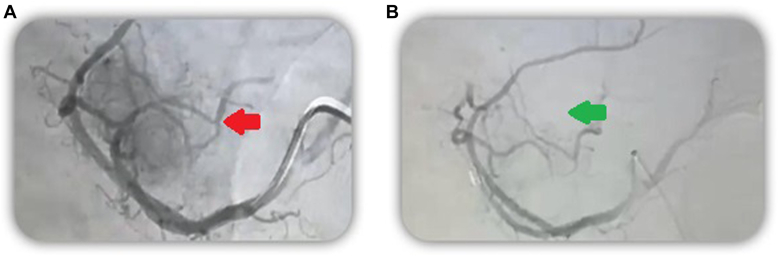

We describe the case of an elderly male patient with multiple comorbidities and recurrent isolated insulinoma of 3.7 × 3.5 cm involving the uncinate process of the pancreas and contacting the splenomesenteric confluent many years after first resection, in whom, after refusing surgical management, was performed as successful arterial embolization of the pancreatic tumor.